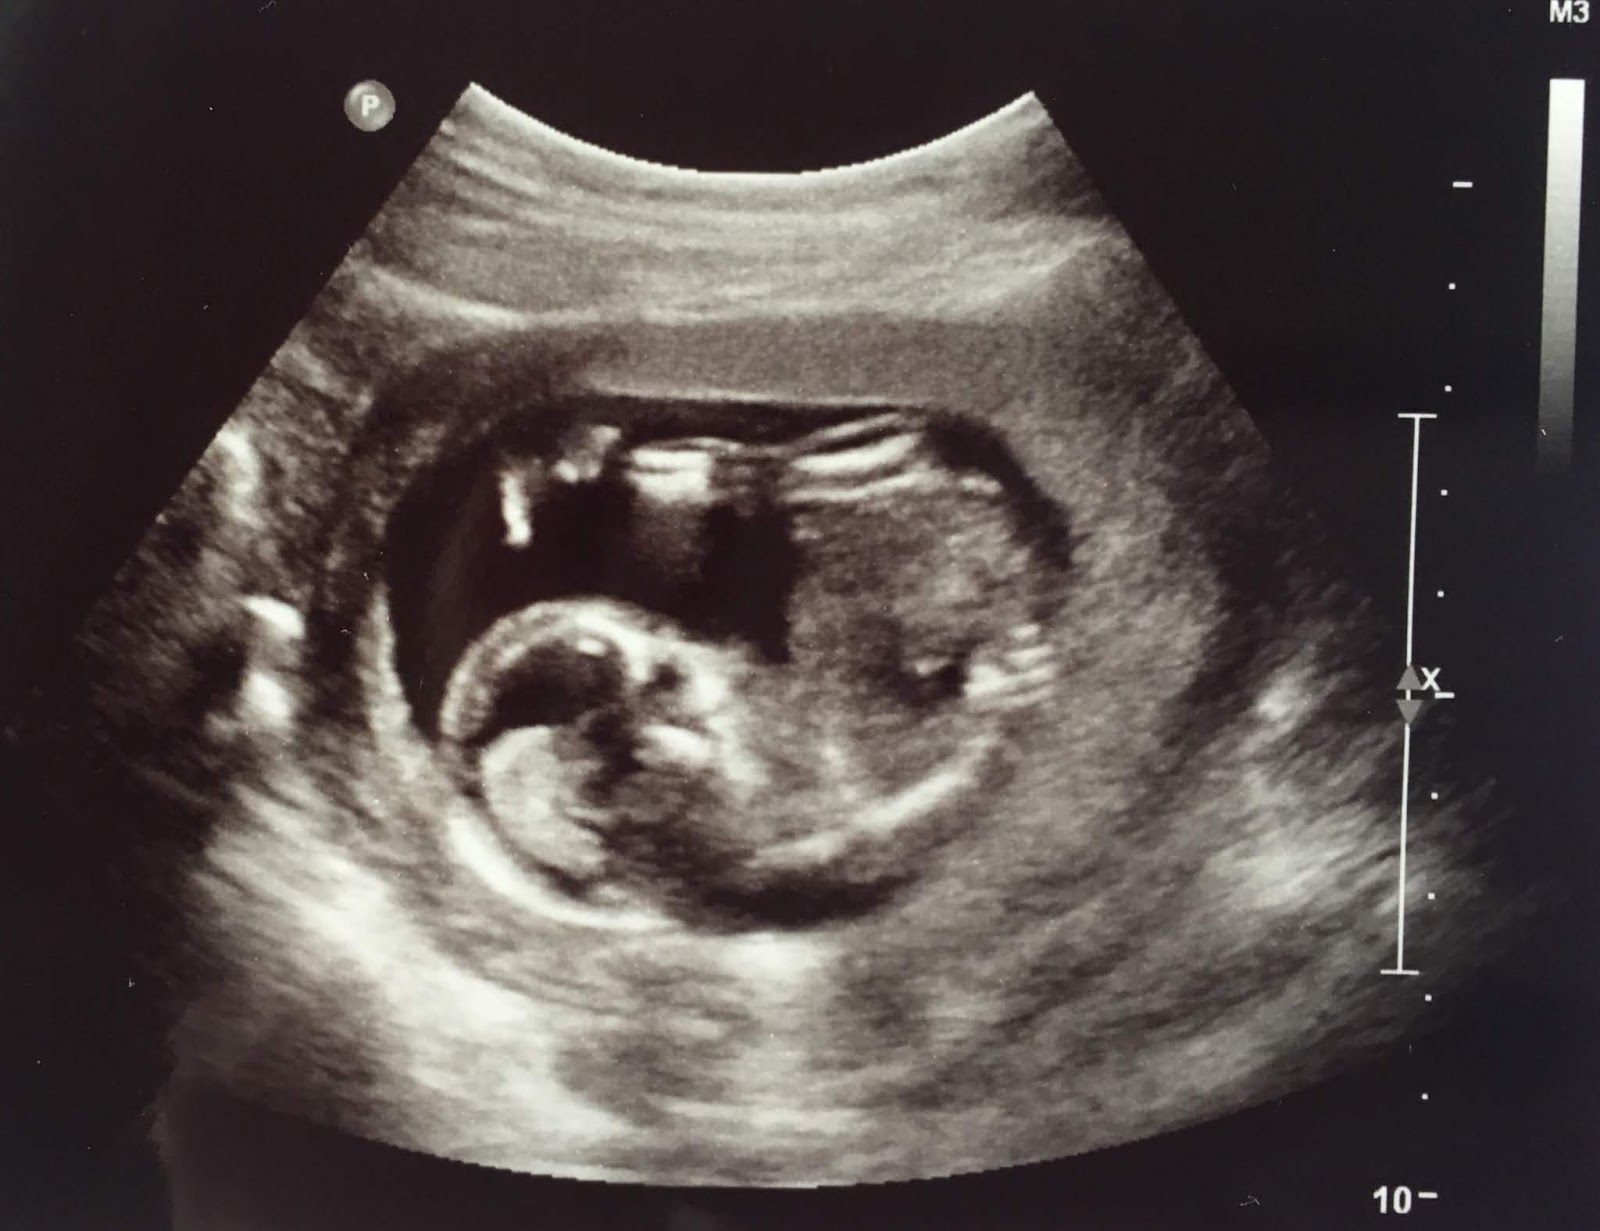

| An ultrasound of an unborn baby. He or she is about 12 weeks old. |